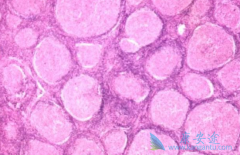

不同的给药途径会影响药物在体内的有效浓度,与疗效关系密切,用药合理与否,关系到治疗的成败。 来那度胺 (Revlimid)作为靶向药,一半是持续使用,直至肿瘤进展或患者不耐受。那来那度胺的吃法与治疗效果有关系吗?来那度胺在治疗多发性骨髓瘤与套细胞 ...

来那度胺 (瑞复美)作为沙利度胺的类似物,为了防止来那度胺可能会导致胎儿出现缺陷或死亡。所以,育龄中的女性在使用来那度胺前都必须进行以下事项:妊娠检测根据当地医疗实际,必须在医生监督下对有可能怀孕的女性进行妊娠检测,要求检测的灵敏度至 ...

来那度胺 (雷利米得)是一种免疫调节药物,该药物具备多种作用机制,在分子水平上,来那度胺已被证明与泛素E3连接酶相互作用并靶向该酶降解Ikaros转录因子IKZF1和IKZF3。也就是说来那度胺的致畸和抗肿瘤性质是可以被分离。因此后期来那度胺逐渐从血液 ...

说到 来那度胺 (lenalidomide),为人熟知的就是在治疗多发性骨髓瘤和骨髓异常综合征的疗效显著;最新的一项研究表明,在治疗肝癌的过程中,来那度胺也发挥重要作用。一项研究中将40例多吉美治疗失败的晚期肝癌患者作为研究对象,观察来那度胺25mg,一天一 ...

雷利度胺 (来那度胺)是一种作用机制比较复杂的药物,其作用包括抑制肿瘤坏死因子а、白介素-6和IL-12,诱导Caspase-8介导的凋亡、抑制细胞黏附和血管生成,通过诱导白介素-2和干扰素г刺激T和NK细胞增殖,抑制Akt磷酸化等。很多患有骨髓增生异常综合 ...